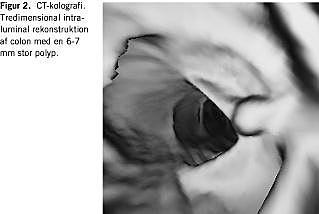

CTK er undersøgt tidligere og mere ekstensivt end MRK. Med hensyn til den diagnostiske præcision er der ingen studier, hvor man direkte sammenligner CTK og MRK. Begge er sammenlignet med koloskopi, og der synes ikke at være betydende forskel. På grund af variation i resultater og forskelle i metode og design i den foreliggende litteratur er et sammenfattende skøn over diagnostisk præcision behæftet med en betydelig usikkerhed [1-3]. Sensitiviteten og specificiteten for CTK/MRK synes dog at være på hhv. ca. 90% og knap 100% ved diagnostik af patienter med tumorer ≥ 1 cm, hhv. ca. 80% og ca. 90% for patienter med tumorer > 5 mm og betydelig lavere for mindre og flade læsioner. Med en undtagelse [4] er alle studier udført på populationer med en høj risiko for polypper eller en selektion af patienter med tumorer. Det er derfor usikkert, om disse resultater kan reproduceres i daglig klinik. Når det i andre studier er fundet, at man med CTK/MRK kan erkende den proksimale colon visuelt efter ufuldstændig koloskopi, f.eks. oralt for en strikturerende tumor hos ca. 90%, er der også tale om selektion, men her helt komplementært til den kliniske situation. Da ulemperne ved CTK/MRK tillige får mindre vægt, når alternativet har svigtet, findes indikationen »inkomplet koloskopi«« at være veldokumenteret. Blandt andet på grund af strålerisikoen ved CTK (effektiv dosis er ca. 7 mSv, svarende til den ved røntgen af colon) og prisen for en MRK er undersøgelserne ikke egnet til screening for KRC. Foreliggende evidens muliggør endnu ikke konklusioner om, hvorvidt teknologien bør have en plads i diagnostik og kontrol af polypper og/eller KRC [3-5] (Figur 2 ).